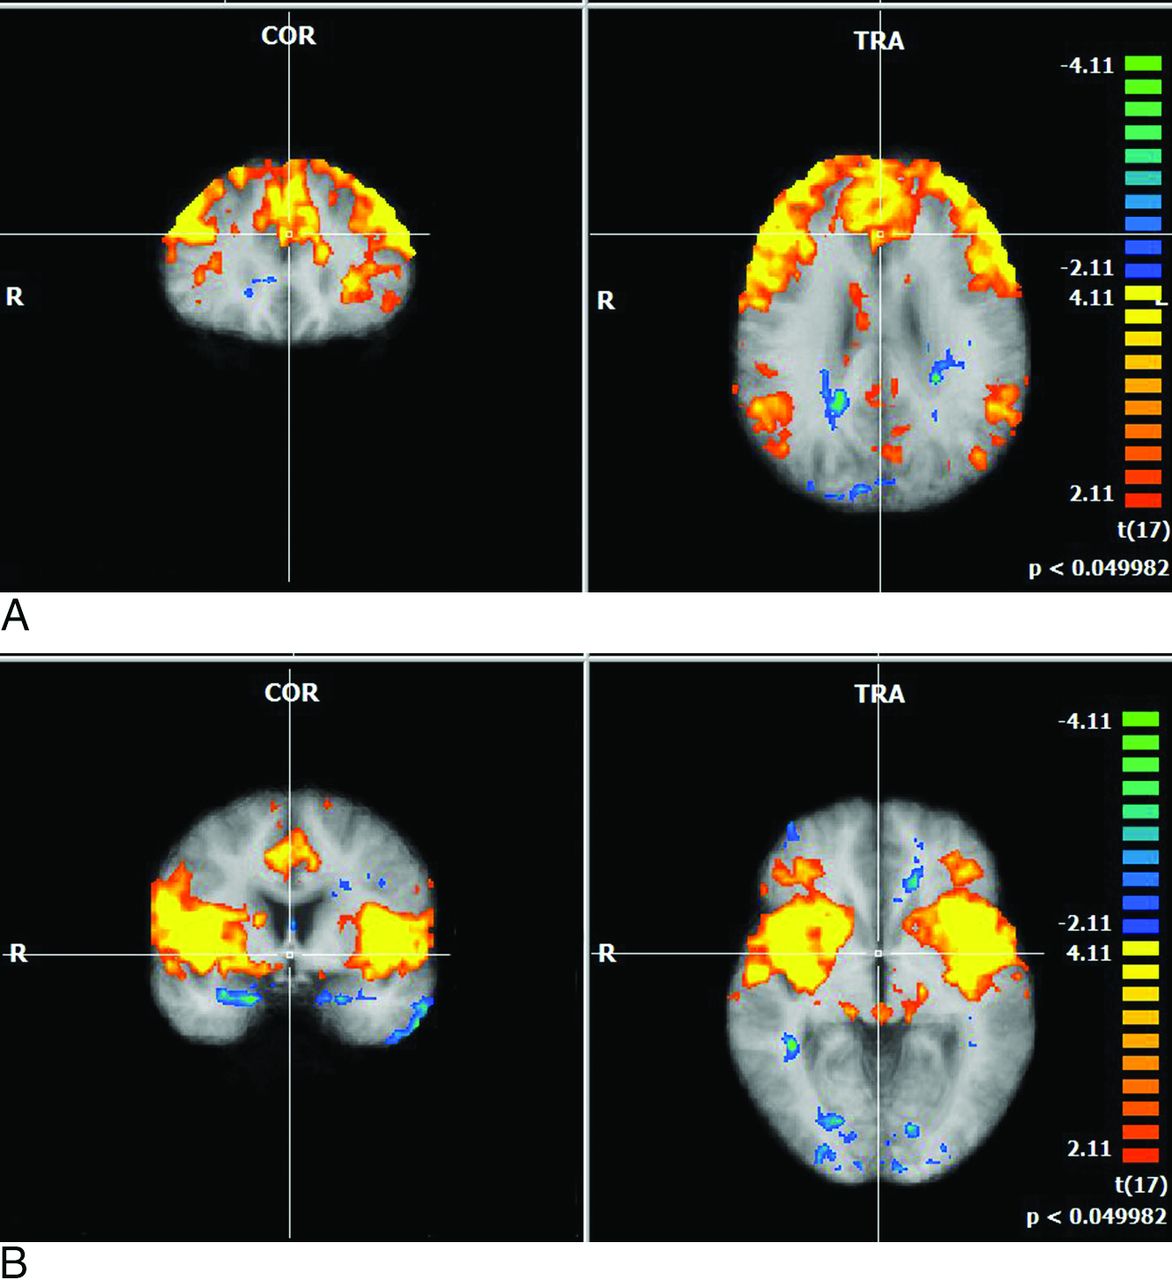

A, Multiplanar depictions of group effect in subjects with HIV in the executive networks with the seed region in Brodmann area 9. Note large consistently activated voxels in the entire group, with activation in the dorsolateral frontal cortex and posterior inferoparietal regions and in the striatum. B, Multiplanar depictions of group effect in subjects with HIV in the executive networks with seed regions in Brodmann area 13. Large consistently activated voxels in the group with activation in the anterior insula, anterior cingulate, and thalamus.

We assessed whether observed changes in brain networks were associated with neuroinflammatory markers (namely CSF and plasma neopterin and β-2 microglobulin) and NC scores. None of the networks demonstrated any significant positive or negative correlations with plasma/CSF biomarkers. However, neurocognitive scores showed significant correlations with all 6 mentioned networks. Within these networks, the salience networks demonstrated the most significant correlations with reduced neurocognitive scores (Figs 3 and 4).

Salience networks. Difference in correlation of the salience network with neurocognitive score (NCS): (Correlation Value in NCS > Median) − (Correlation Value in NCS < median). Orange denotes areas showing larger correlation values in patients with larger neurocognitive values, while blue shows the opposite. Each of the maps is corrected with the cluster-correction approach.

Covariate analysis with neurocognitive scores demonstrating surviving voxels in each of the 6 networks.